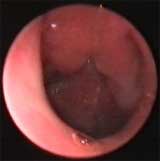

Нормальная барабанная перепонка.(отоскопия — эндоскоп 0°).

Экссудативный отит на фоне хронического аденоидита.(отоскопия — эндоскоп 0°).

На фоне аденоидита часто отмечается возникновения острого и обострения хронического отита. Даже повторяющиеся несколько раз негнойные формы отитов, могут привести к кондуктивной тугоухости. Хроническое воспаление аденоидных вегетаций играет большую роль в патогенезе экссудативного отита, как резервуар для Haemophilus influenzae, отодвигая значение величины миндалины на второе место.